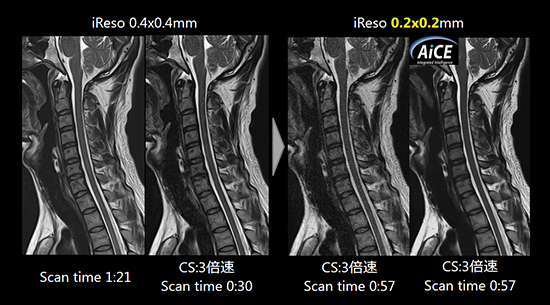

Compressed SPEEDER

パラレルイメージング法と圧縮センシング法を組み合わせた高速撮像法により,画質劣化を抑えた高速化を実現します。さらにAiCEとの組み合わせにより高画質化と高速化を高い次元で両立します。